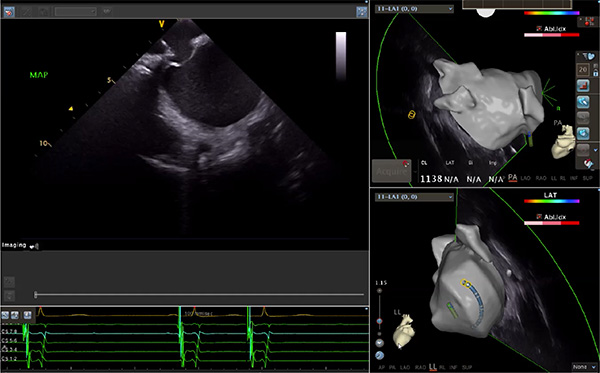

超聲心動圖技術包括常規(guī)經(jīng)胸超聲(TTE)、經(jīng)食管超聲(TEE)、心腔內(nèi)超聲(ICE)、超聲聲學造影(MCE)、三維超聲心動圖等,ICE是一種新興技術——將微型的換能器安裝在心導管的尖端,經(jīng)由外周血管輸送至心腔內(nèi)部,換能器發(fā)射聲波,對心臟及其鄰近組織進行實時高質(zhì)量成像和(或)血流動力學測定的超聲成像技術?;诓煌募夹g原理,心腔內(nèi)超聲導管被分為兩類:機械旋轉式超聲導管和相控陣超聲導管。目前,臨床上主要應用的是相控陣超聲導管,ICE成像通過術者旋轉導管及操縱導管手柄上的兩個旋鈕來完成。

ICE門檻高、集成了超聲和圖像處理最前端的技術,是當前內(nèi)窺超聲方向最挑戰(zhàn)的領域。不同于傳統(tǒng)接觸式三維重建方法會產(chǎn)生假腔,影響術者對靶點或結構的判斷,心腔內(nèi)超聲(ICE)可直接顯示心臟結構,有助于理解心臟內(nèi)各部位之間的解剖關系,不僅具有實時成像、并發(fā)癥監(jiān)測以及良好的耐受性,同時以股靜脈入路,無需全麻或深度鎮(zhèn)靜,日益成為心臟介入手術中重要輔助工具,被譽為心臟介入醫(yī)生的“黃金眼”。心腔內(nèi)超聲可用于多種心臟介入手術,潛在患者群體龐大,動脈網(wǎng)測算我國心腔內(nèi)超聲導管市場空間或將超100億元,具有廣闊前景。

隨著心腔內(nèi)超聲的應用更廣,性能也在逐漸優(yōu)化,已從二維成像轉變?yōu)?strong>三維成像,極大增強了引導及可視化能力。二維心腔內(nèi)超聲支持雙平面或三平面成像,可顯示兩個或三個不同的平面視圖,但醫(yī)生需將這些圖像在腦海中重新構建為三維解剖結構。三維心腔內(nèi)超聲則可直接呈現(xiàn)三維解剖結構圖,便于醫(yī)生更輕松地開展手術。按照產(chǎn)品發(fā)展方向,預計心腔內(nèi)超聲還將向更清晰、精準、多功能等方向發(fā)展。